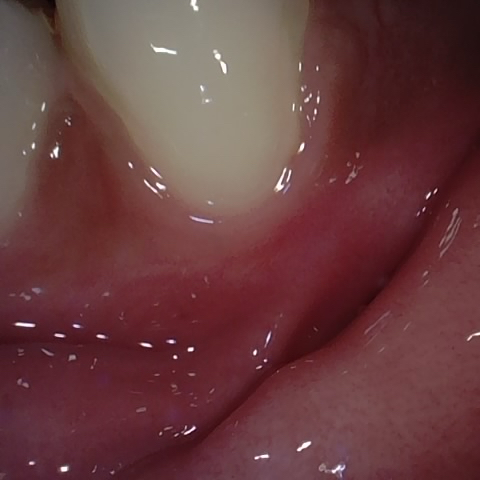

Annotated as "Bad"